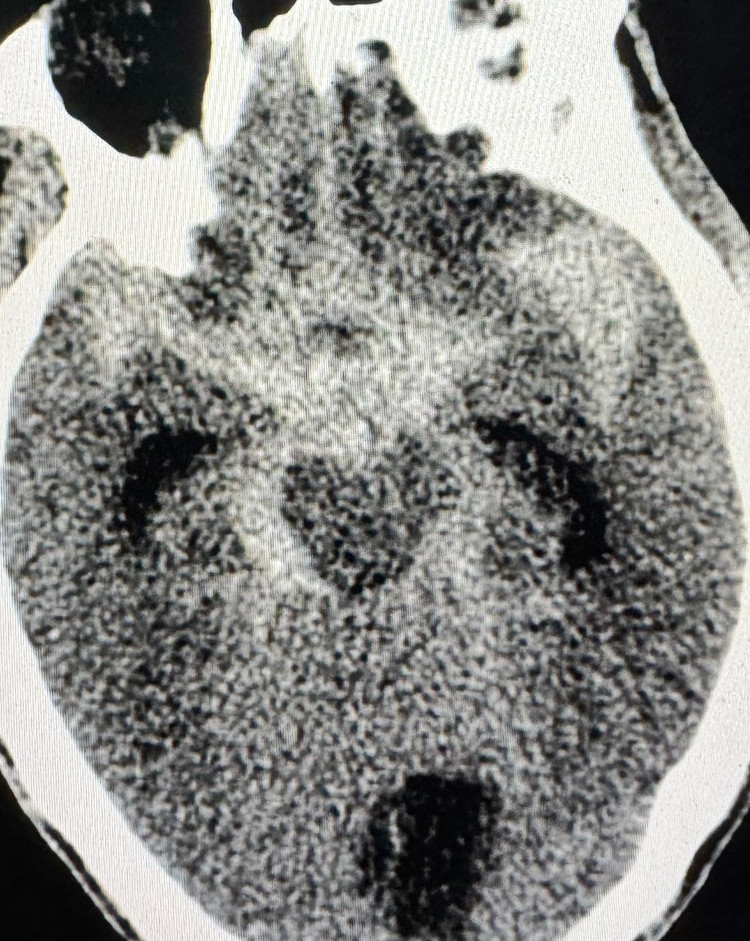

Ngay khi tiếp nhận bệnh nhân các bác sĩ tiến hành đặt nội khí quản và thực hiện các cận lâm sàng. Kết quả chụp CTA (CT scanner) xuất huyết dưới nhện lan toả tràn máu não thất (mFISHER 4) do vỡ túi phình động mạch thông trước và đỉnh thân nền.

| Vỡ túi phình đỉnh thân nền trên phim chụp - Ảnh BVCC |

Các bác sĩ đã hội chẩn cùng chuyên gia Trung tâm điện quang Bệnh viện Bạch Mai xác định bệnh nhân xuất huyết dưới nhện do vỡ túi phình đỉnh thân nền, nguy cơ tử vong rất cao nếu không can thiệp.

Dưới Hệ thống chụp mạch máu số hoá xoá nền DSA hình ảnh 4 túi phình mạch não của bệnh nhân được phát hiện: 01 túi phình vị trí động mạch thông trước và 02 túi phình vị trí đỉnh thân nền, gốc động mạch tiểu não trên trái, đáy nhọn nguy cơ vỡ cao, 01 túi phình nhỏ 3x4mm đoạn tận M1 động mạch não giữa trái, bờ đều, ít nguy cơ.